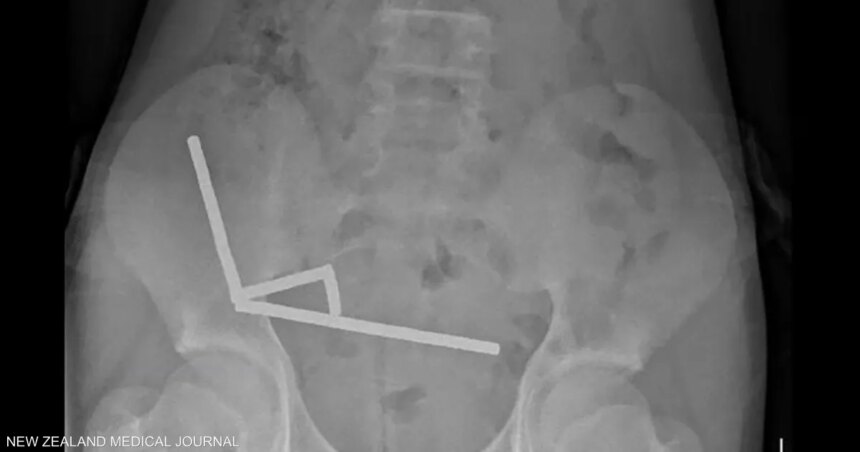

وأظهرت الأشعة أن المغناطيسات تكتلت معا في 4 خطوط مستقيمة داخل أمعاء المراهق، و”يبدو أنها كانت في أجزاء منفصلة من الأمعاء ملتصقة ببعضها البعض بسبب القوى المغناطيسية”، وفق الأطباء.